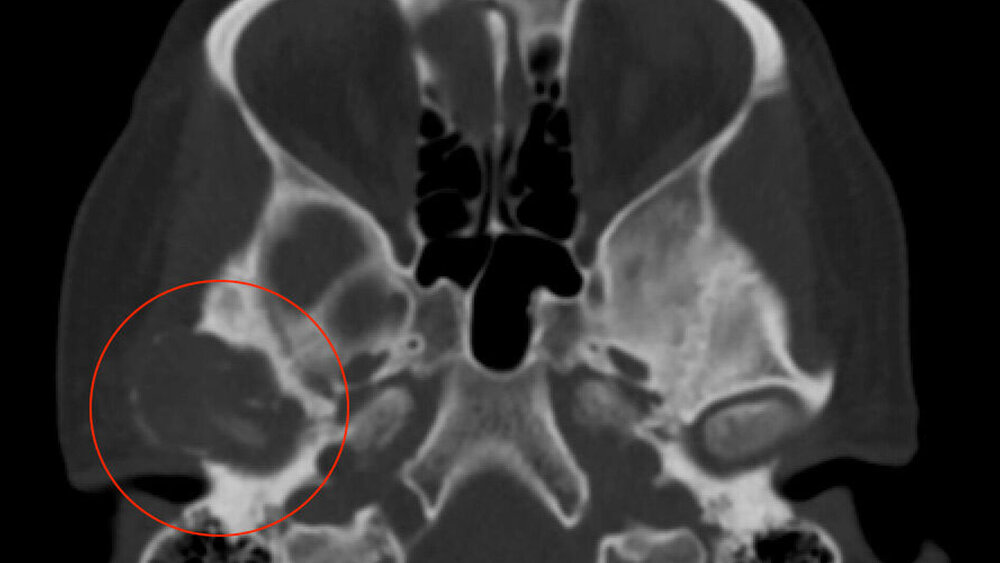

Zufallsbefund eines Riesenzelltumors bei langjähriger Bruxismus-Patientin